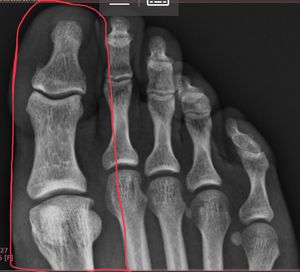

Injured right foot 1st Proximal Phalanx

Do you guys see any abnormality? Patient complaints of pain after accidentally kicking concrete, swollen and unable to bend. Maybe a metartasophalangeal articular capsule of hallux injury/dislocation?